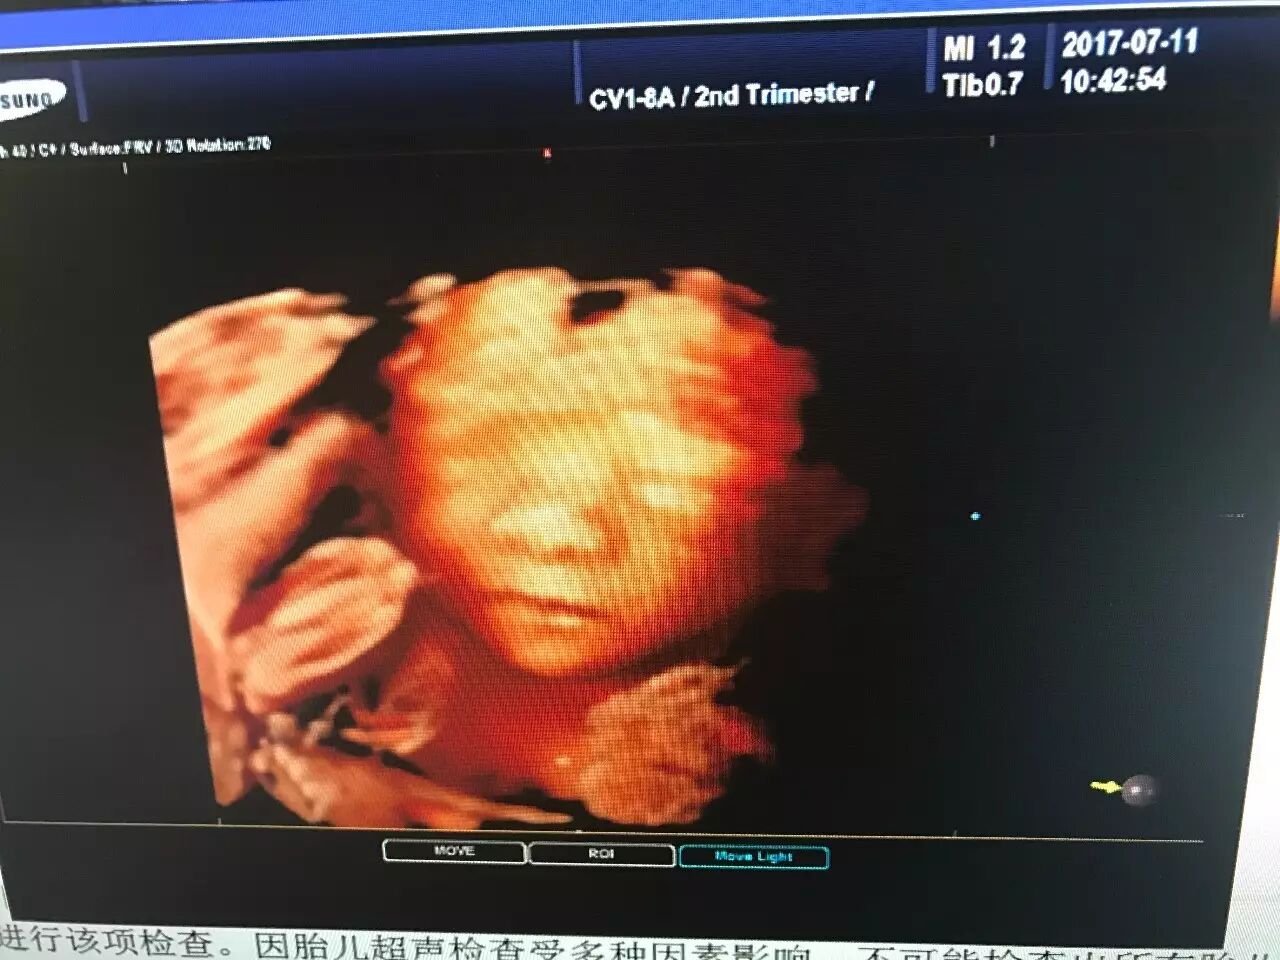

爸爸妈妈用仁德医院的超高端四维彩超

看到的我是酱紫的

(图片来自仁德医院彩超室)

★四维彩超:“4D”是“四维”的缩写,也被称作实时三维。对于超声学来说,4D超声技术是彩超行业的革命性突破。就像是摄像机所拍摄所拍摄到的画面。看到的是立体图像,能看到胎儿的上下左右前后的情况,能更加准确的看到胎儿的情况。

★超高端四维彩超:是采用4D超声图像加上空间维度参数,获取更加立体、逼真的四维图像,超越了传统灰阶超声的大部分限制。其结果是:能够栩栩如生的显示宝宝在妈妈肚子里的实时动态活动高仿真图像,精准排查胎儿畸形。